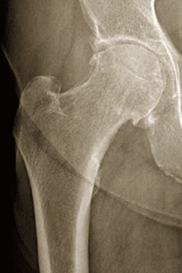

À l’examen, le genou est sec et indolore à la mobilisation. Il n’y a pas de kyste poplité. Cependant, la mobilisation de la hanche montre un syndrome clinostatique franc (impossibilité pour le patient de décoller le talon du plan du lit, jambe tendue, allongé sur le dos) en faveur d’une atteinte de l’articulation coxofémorale. Celle-ci est suspectée devant une limitation douloureuse des amplitudes de la hanche droite, notamment en abduction et rotation interne. Le cliché suivant a été réalisé au décours de la consultation.

Coxarthrose droite avec pincement coxo-fémoral et ostéophytes. Toute gonalgie doit faire évoquer une atteinte de l’articulation sus-jacente avant traitement.